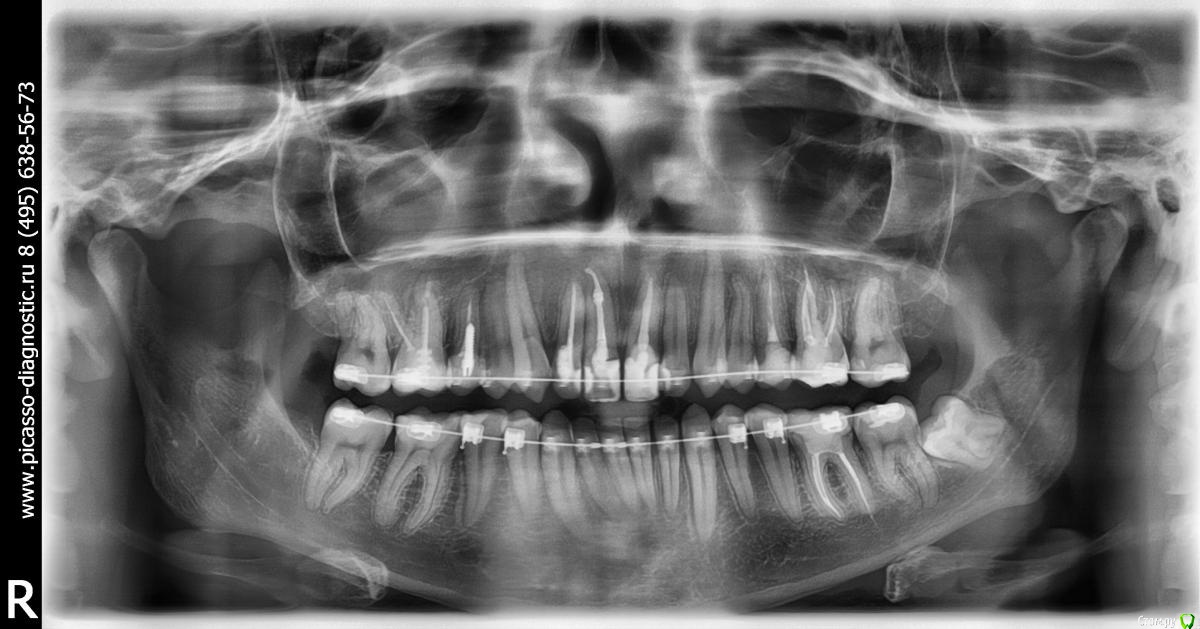

Добрый день ! Мне 29 лет. Ношу брекеты 10 мес. На данном этапе лечения сделали панорамный снимок, чтобы посмотреть ровно ли стоят корни зубов. После этого врач решил переклеить один брекет на клыке ( на снимке его видно слева ). А мне по снимку бросились в глаза , помимо этого клыка, рядом стоящий боковой резец ( он же не нравится мне как стоит и внешне) , и на нижней челюсти : 1- ый премоляр,и рядом стоящие 3 резца. Врач сказал подумать неделю и решить, хочу ли я переклеить или нет какой либо из брекетов,тк дальше они так и останутся. На её взгляд ничего переклеивать , кроме клыка, больше не нужно.

П.с. На нижн. челюсть уже поставили резинки для стягивания щелей. Я так понимаю после этого этапа уже на них брекеты не будут переклеиваться ?

Главный вопрос : Нужно ли мне переклеивать еще какие- нибудь брекеты , опускать или поднимать какой- либо из зубов, чтобы добиться большей эстетики и в дальнейшем правильного прикуса ? Или же не нужно. Заранее спасибо за внимание.